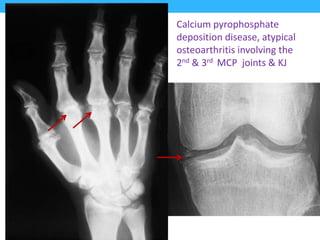

• 2nd and 3rd mcp joints, are usually the first

joints involved.

• Calcium pyrophosphate (chondrocalcinosis or

pseudogout), mainly in the knee.

Calcium pyrophosphate

deposition disease, atypical

osteoarthritis involving the

2nd & 3rd MCP joints & KJ